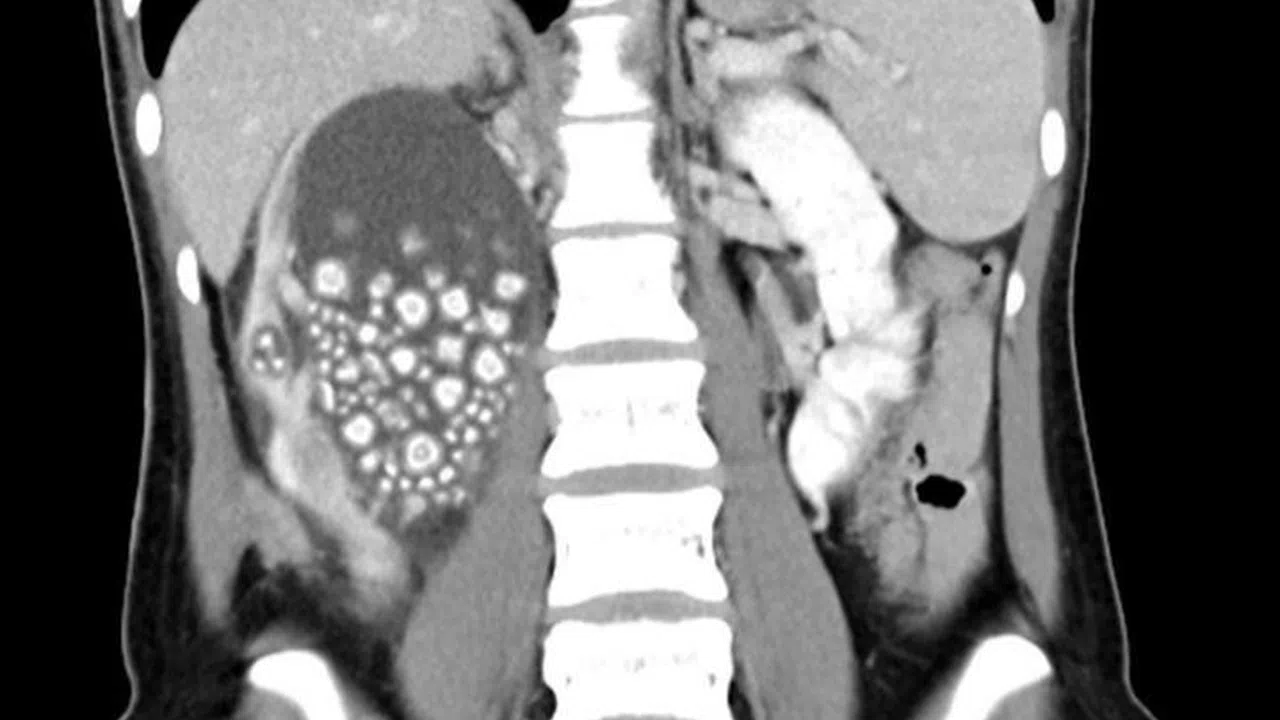

Tayvan’ın güneyinde yer alan Tainan şehrinde 20 yaşındaki Xiao Yu adlı biri sırt ağrısı şikayetiyle Chi Mei Hastanesi'ne başvurdu. Tetkiklerin sonucunda böbreklerinde çok sayıda böbrek taşı tespit edilen Yu acil ameliyata alındı. Başarılı geçen ameliyatın ardından Xiao Yu’nun böbreklerinden 0.5-2 cm boyutlarında 300’den fazla böbrek taşı çıkarıldı.